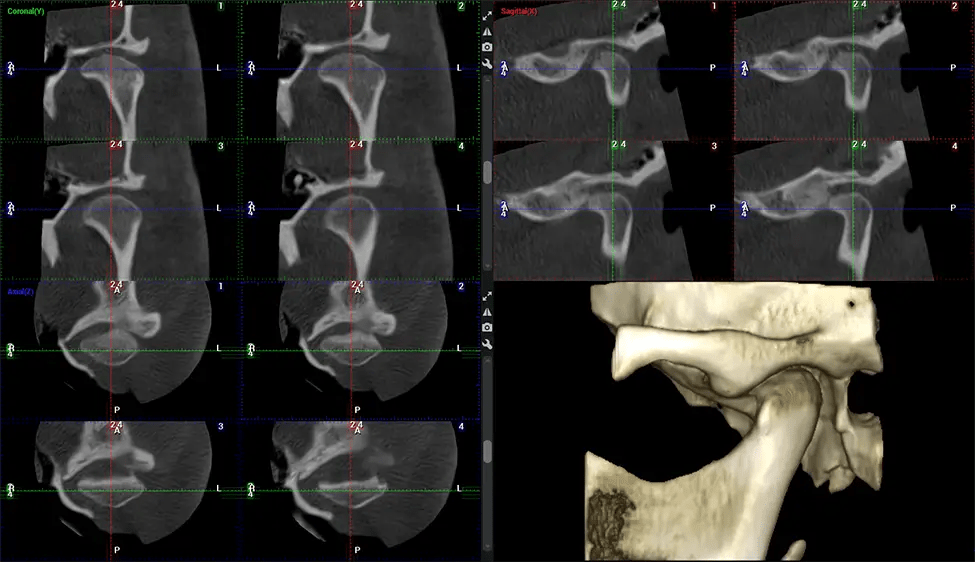

There are many benefits to using CBCT technology, especially compared to the traditional 2D X-ray format. One of the most significant advantages of CBCT scans is that they provide much more information than traditional X-rays. A scan lets your dentist see images from all angles of your jaw and mouth, including your sinuses, nasal cavity, cheekbones, and other surrounding areas. This added information helps your dentist craft a comprehensive treatment plan that addresses all aspects of your oral health.

Another significant benefit is that 3D imaging provides more precise images of your bone structure. These images are more detailed, providing you with a more accurate diagnosis. An accurate diagnosis means better treatment for you.

When paired with extractions, dental implant placement, or bone grafting, CBCT technology can provide you with a quicker and much more comfortable experience. This is because the 3D image provides a more detailed picture of your entire oral cavity, allowing your dentist to walk you through each step of the process before it occurs. This often helps patients feel more prepared and comfortable overall, especially if they have had a traumatic experience with past dental treatments.